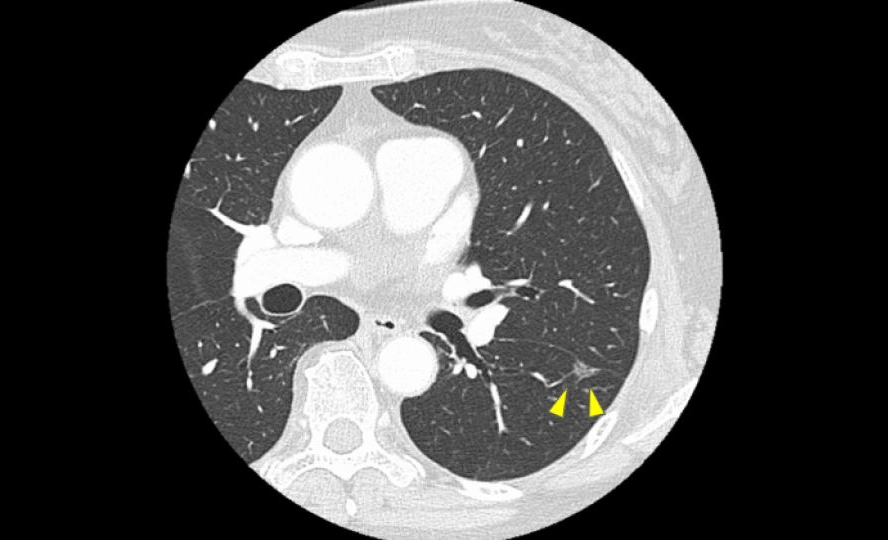

5. 図1.2 のように“早期に見つかる影”で多い相談

図1

図2

近年はCTで、症状が出る前の小さな影が見つかることが増えています。というより、初期の肺がんでは症状が出ないことが多いです。この段階では「すぐ治療」ではなく「まずはCTで経過観察」と言われることも珍しくありません。

ちなみに、先ほど示した図1、2に関しては手術を行い、病理検査の結果いずれも「肺癌」と診断されました。